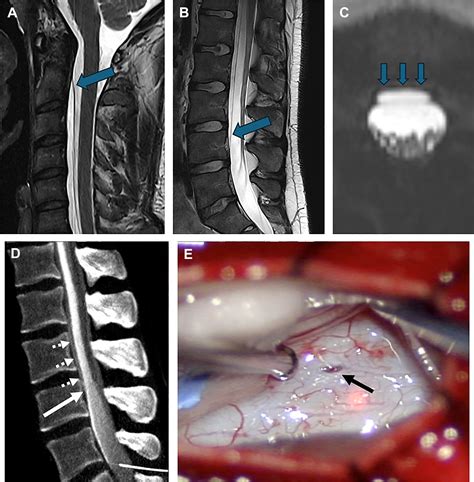

The Cerebrospinal Fluid Halo Sign occurs due to the displacement of CSF around a lesion. This displacement can be caused by various factors, including the growth of a tumor, the formation of an abscess, or the presence of a cyst. The CSF halo is typically visualized on MRI scans as a low-intensity signal surrounding the lesion, contrasting with the higher-intensity signal of the lesion itself. This contrast helps radiologists and neurologists to identify the presence and extent of the lesion more accurately.

Advanced imaging techniques, particularly MRI, are essential for visualizing the Cerebrospinal Fluid Halo Sign. MRI provides high-resolution images of the brain, allowing for the detailed examination of lesions and their surrounding tissues. The use of contrast agents, such as gadolinium, can further enhance the visibility of the CSF halo and other abnormalities.

Other imaging techniques, such as computed tomography (CT) scans, may also be used in conjunction with MRI to provide a comprehensive assessment of the brain. However, MRI is generally preferred for its superior soft-tissue contrast and ability to detect subtle changes in the brain.